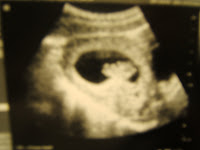

Here are the first pictures I have of my baby (to clarify, now when I say "my baby" I am not speaking of Diggy :) For those who don't know, which I'm pretty sure anyone that reads this does, I'm 12 weeks pregnant. The baby will be here in August! We are excited!

I'll answer the main questions people ask me: I am very excited, Adam's excited, it was a "planned" pregnancy (although a bit sooner than we were expecting), we are finding out the sex (beginning of March), I don't have names picked out yet but definitely have a mental list (waiting to battle that one out with Adam after we find out the sex), I don't care what it is, the due date is either July 27 or August 14 (they have given me both based on my cycle and the size of the baby, so who really knows), and I think that's it.